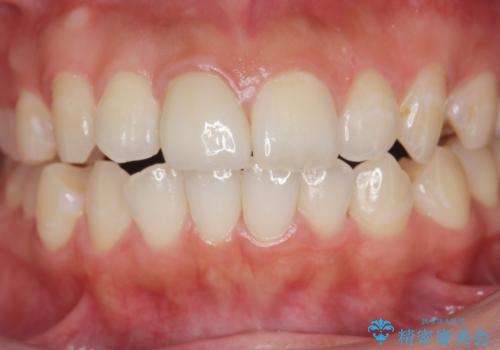

周囲の歯の色調に調和した審美性の高いセラミッククラウンを製作することができました。